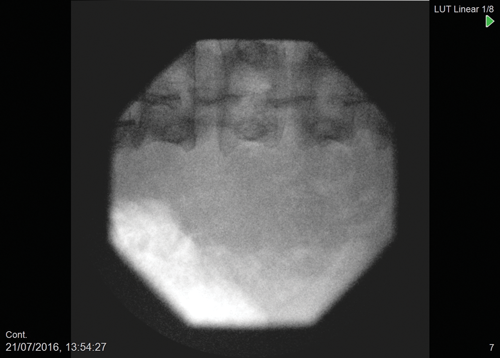

The 3.5Fr ultramini nephroscope is then passed into the diverticulum with saline irrigation (Figure 2). Blood clots from the percutaneous puncture can be removed using the vortex effect or using a tipless basket e.g. Zerotip™ (Boston Scientific, USA). Once the calculus has been identified a 200 micron laser fibre can then be inserted down the working channel of the nephroscope to fragment the calculus. Fragments can then be removed with either basket or vortex effect (Figure 3).

Figure 3: Stone free after laser fragmentation; tubeless procedure.

Post standard PCNL, a nephrostomy tube is left with the intention of tamponading any bleeding from the dilated access tract, which is usually 30Fr, and to allow free drainage of the collecting system and maintain access if a second procedure is required. Studies have shown that a totally tubeless approach has not led to any patient compromise [18]. Using the ultramini PCNL, as the tract is small there is no requirement for placement of a nephrostomy tube postoperatively as long as there are no intraoperative concerns with bleeding. The ureteric catheter plumbed into the urethral catheter can be left as a temporary stent for 12-24 hours if necessary.